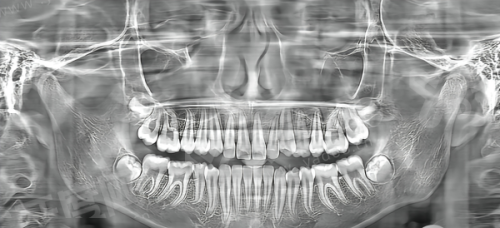

(三)西捷美牙冠临床适用人群与修复成效

1、对于前牙美学修复,西捷美全瓷冠的透光性和色泽层次感表现优异,能够良好地模拟天然牙的质感,避免“假白”现象。

2、在后牙咀嚼功能修复上,其材料强度足以应对日常饮食需求,适合大多数单颗缺失或根管治疗后的牙齿保护。

3、特别适合对金属过敏的人群,因为它是纯全瓷材质,不含任何金属内冠,做核磁共振检查时也不会产生伪影干扰。

1、潜在局限:虽然西捷美的硬度足够日常使用,但对于有重度夜磨牙习惯或咬合力极大的患者,其抗折裂能力略逊于部分精品进口高强度氧化锆。

2、注意事项:在做长桥连修复(即一次性修复多颗连续缺失牙)时,需要医生严格评估基牙条件,不建议跨度太大,以免增加断裂风险。